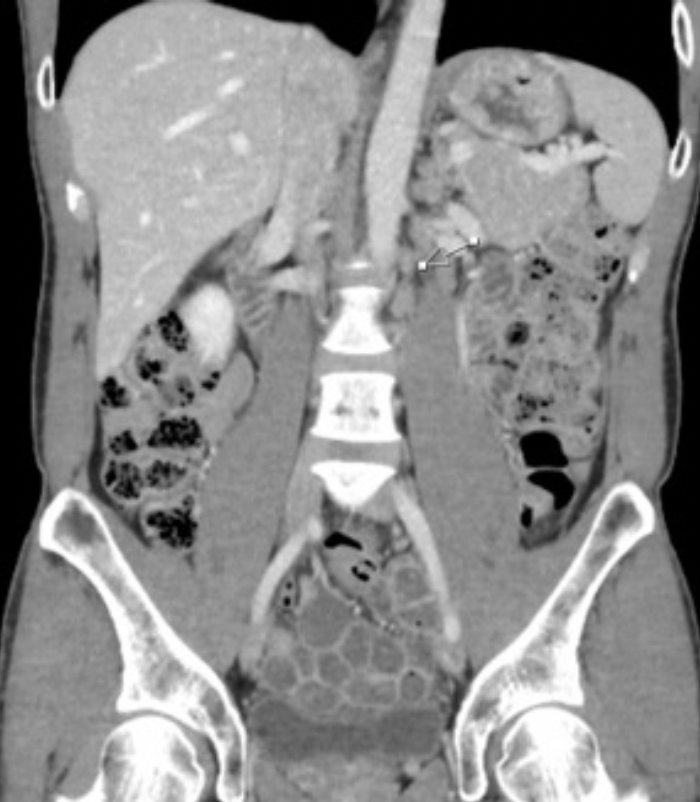

A CT scan of the chest/abdomen/pelvis 1 month after the CT scan of the neck confirmed the neck lymphadenopathy as well as several foci of left retroperitoneal periaortic lymph nodes that were enlarged, all less than 2 cm in greatest dimension (Figure 2).

FIGURE 2. Coronal CT Abdomen and Pelvis Showing Several Foci of Periaortic Lymphadenopathy